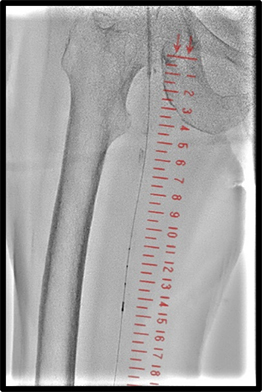

その他、当院で実際に使用した臨床例について示す。(図10、図11、図12)

IGS630_Fukaya_15.jpg図12 VAIVT